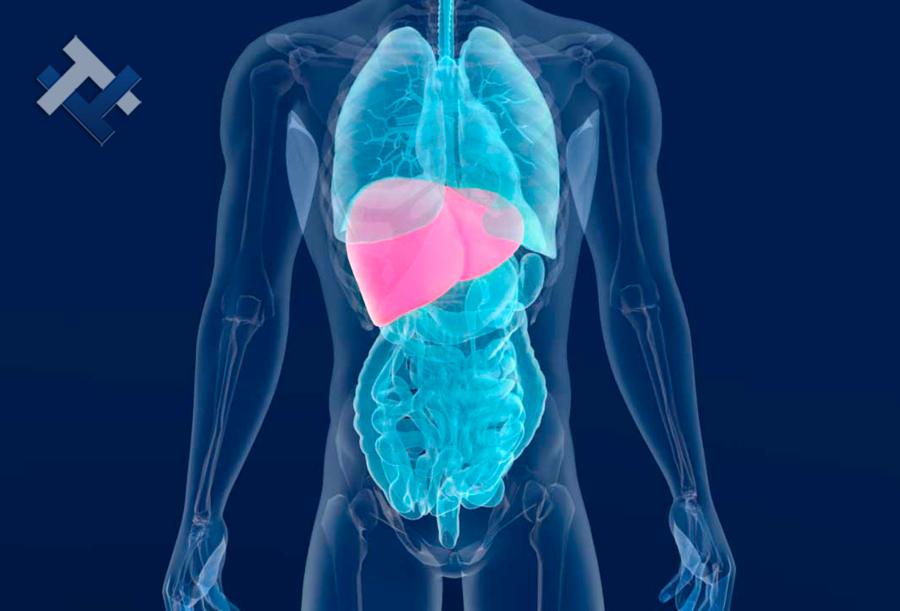

Ο Γενικός Χειρουργός Λιάγκος Γεώργιος MD PhD εκτελεί τις επεμβάσεις Λαπαροσκοπικά, Ενδοσκοπικά, Ανοιχτά Ελάχιστα Επεμβατικά και με Laser. Η θεραπεία εξατομικεύεται σε κάθε ασθενή ανάλογα με τις ανάγκες του. Αναλαμβάνει περιπτώσεις όπως κήλες και κοιλιοκήλες (αντιμετώπιση βουβωνοκήλης, αντιμετώπιση ομφαλοκήλης, θεραπεία επιγαστρικής κήλης, κήλη των αθλητών (Σύνδρομο κοιλιακών προσαγωγών), αντιμετώπιση μετεγχειρητικής κήλης, θεραπεία Μηροκήλης), πέτρες στη χοληδόχο κύστη, λαπαροσκοπική χολοκυστεκτομή, αντιμετώπιση Κύστη Κόκκυγος με λέιζερ (laser), παθήσεις πρωκτού, χειρουργική laser σύγχρονων κυκλικών ινών (αιμορροΐδες αντιμετώπιση, θεραπεία αιμορροϊδων με laser (LHP), αφαίρεση αιμορροΐδων με υπερήχους (HALL-RAR), χωρίς Χειρουργείο με ελαστικούς δακτυλίους (Τεχνική BARON-RBL), θεραπεία ραγάδας πρωκτού (Ραγάδα δακτυλίου), θεραπεία περιεδρικού συριγγίου, θεραπεία περιεδρικού αποστήματος, κονδυλώματα πρωκτού Θεραπεία, δερματικό ράκος (Skin tag) εκτομή, αντιμετώπιση Kνησμού, καρκίνος πρωκτού θεραπεία), παθήσεις Δέρματος, χειρουργική με laser CO2, αφαίρεση μορφωμάτων δέρματος - βιοψίες, αφαίρεση ελιάς (Σπίλου), σμηγματογόνος κύστης θεραπεία, αφαίρεση λιπώματος, είσφρυση όνυχος χειρουργείο, καρκίνος δέρματος θεραπεία, οξεία σκωληκοειδίτιδα, παθήσεις Λεπτού και Παχέος Εντέρου, ειλεός λεπτού εντέρου, εκκολπωμάτωση (Εκκολπωματίτιδα) σιγμοειδούς, καρκίνος παχέος εντέου, κολοστομίες, port χημειοθεραπείας κ.α.

Ο Γενικός Χειρουργός Λιάγκος Γεώργιος MD PhD εκτελεί τις επεμβάσεις Λαπαροσκοπικά, Ενδοσκοπικά, Ανοιχτά Ελάχιστα Επεμβατικά και με Laser. Η θεραπεία εξατομικεύεται σε κάθε ασθενή ανάλογα με τις ανάγκες του. Αναλαμβάνει περιπτώσεις όπως κήλες και κοιλιοκήλες (αντιμετώπιση βουβωνοκήλης, αντιμετώπιση ομφαλοκήλης, θεραπεία επιγαστρικής κήλης, κήλη των αθλητών (Σύνδρομο κοιλιακών προσαγωγών), αντιμετώπιση μετεγχειρητικής κήλης, θεραπεία Μηροκήλης), πέτρες στη χοληδόχο κύστη, λαπαροσκοπική χολοκυστεκτομή, αντιμετώπιση Κύστη Κόκκυγος με λέιζερ (laser), παθήσεις πρωκτού, χειρουργική laser σύγχρονων κυκλικών ινών (αιμορροΐδες αντιμετώπιση, θεραπεία αιμορροϊδων με laser (LHP), αφαίρεση αιμορροΐδων με υπερήχους (HALL-RAR), χωρίς Χειρουργείο με ελαστικούς δακτυλίους (Τεχνική BARON-RBL), θεραπεία ραγάδας πρωκτού (Ραγάδα δακτυλίου), θεραπεία περιεδρικού συριγγίου, θεραπεία περιεδρικού αποστήματος, κονδυλώματα πρωκτού Θεραπεία, δερματικό ράκος (Skin tag) εκτομή, αντιμετώπιση Kνησμού, καρκίνος πρωκτού θεραπεία), παθήσεις Δέρματος, χειρουργική με laser CO2, αφαίρεση μορφωμάτων δέρματος - βιοψίες, αφαίρεση ελιάς (Σπίλου), σμηγματογόνος κύστης θεραπεία, αφαίρεση λιπώματος, είσφρυση όνυχος χειρουργείο, καρκίνος δέρματος θεραπεία, οξεία σκωληκοειδίτιδα, παθήσεις Λεπτού και Παχέος Εντέρου, ειλεός λεπτού εντέρου, εκκολπωμάτωση (Εκκολπωματίτιδα) σιγμοειδούς, καρκίνος παχέος εντέου, κολοστομίες, port χημειοθεραπείας κ.α.